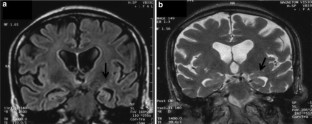

Pompe disease is a rare metabolic disorder, due to mutations in the gene encoding acid alpha-glucosidase (GAA), of which infantile and late-onset forms may occur. Aim of the work was to analyze clinical and laboratory data of a cohort of late-onset Pompe disease (LOPD) patients, collected during the last 15 years and to point out unusual phenotypic/genotypic features as well as enzyme replacement therapy (ERT) responses. We diagnosed 30 LOPD patients; at follow-up, they underwent motor, respiratory, cardiac and muscle MRI evaluations. Motor performances were tested by Walton Gardner-Medwin, GSGC and 6MWT tests. Respiratory function was assessed as FVC % in upright/supine position. LOPD presentations were represented by presymptomatic hyperCKemia (37 %), proximal/axial muscle weakness (53 %) and respiratory impairment (10 %). Median diagnostic delay was 8.6 years (±8.8). Atypical features were observed in 4 patients: marked distal muscle weakness and severe hearing loss at onset, as well as leukoencephalopathy and mesial temporal sclerosis during the disease course. By GAA sequence analysis, two causing mutations were detected in 22/30 patients, only one in the remaining 8 subjects. Overall, 29/30 patients harbored the common c.−32−13T>G mutation (2 were homozygous). Two new DNA variations were discovered (c.2395C>G, c.1771C>T). 14 patients received ERT for up to 60 months. Our study confirms LOPD clinical and genetic heterogeneity: atypical features may contribute to expand the clinical phenotype highlighting its multi-systemic nature. A timely diagnosis could allow early ERT start. An accurate follow-up is recommended to evaluate treatment responses.

Fig. 2